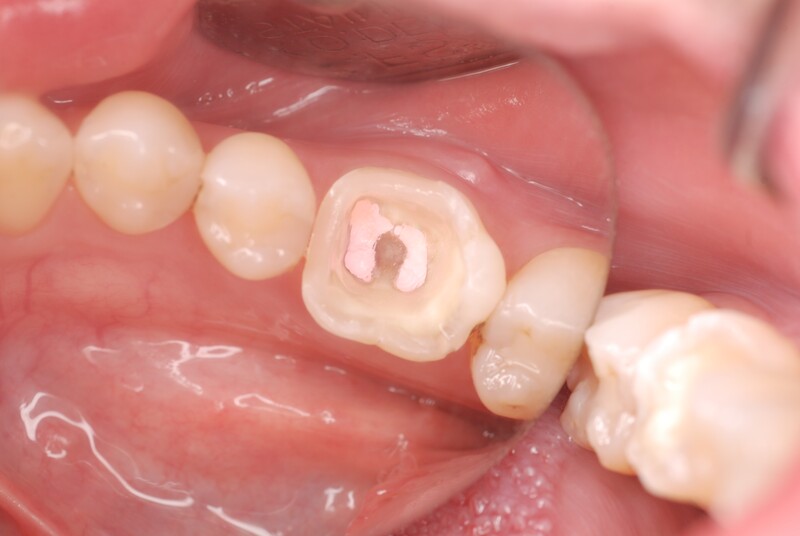

初診時の写真です。歯肉が腫脹しております。

詰め物を外すと虫歯が確認されました。

虫歯を徹底的に除去し、樹脂で補強しました。

ラバーダム防湿下で可能な限り無菌的な環境で根管治療を行いました。

症状およびレントゲン所見が改善されたのを確認し、支台築造を行いました。